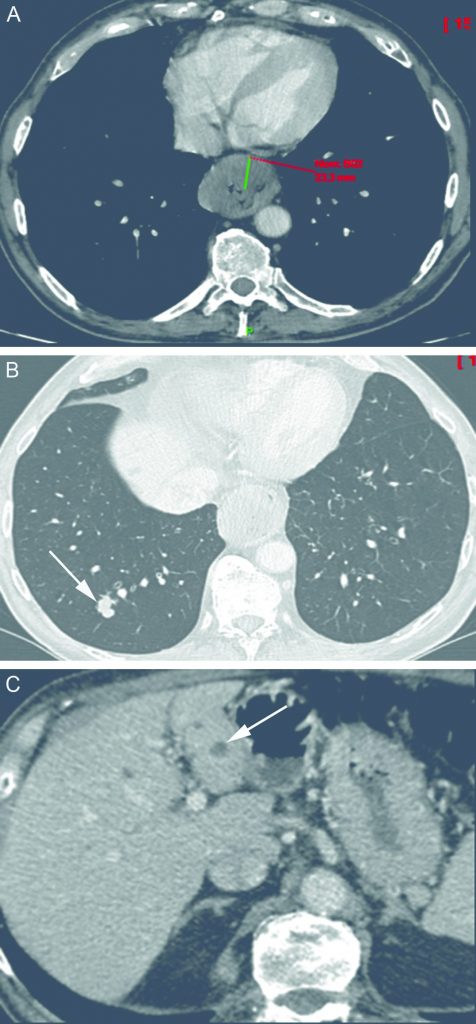

Fig. 17.1. Carcinome épidermoïde de l’œsophage. Scanner au temps portal après injection intraveineuse de produit de contraste iodé. Coupes axiale (A) : le cancer apparaît comme un épaississement circonférentiel de la paroi œsophagienne d’environ 2 cm d’épaisseur responsable d’une sténose. Les coupes passant par le poumon (B) et par le foie (C) montrent des métastases (flèches) qui rendent le patient inopérable.

Source : CERF, CNEBMN, 2022.

La tumeur apparaît au scanner comme une sténose œsophagienne. La paroi de l’œsophage est épaissie, souvent de façon asymétrique, circonférentielle ou non (cf. figure 17.1). En TEP-TDM au 18FDG, elle est fortement hypermétabolique. On apprécie la hauteur de la tumeur et sa localisation précise surtout grace à la TEP (cf. figure 17.2), et son extension aux organes de voisinage surtout grâce au scanner dont la résolution spatiale est plus élevée que la TEP. L’importance de la dilatation d’amont est le reflet de la sévérité de la sténose.

Les sites métastatiques les plus fréquents sont le poumon, le foie et l’os.